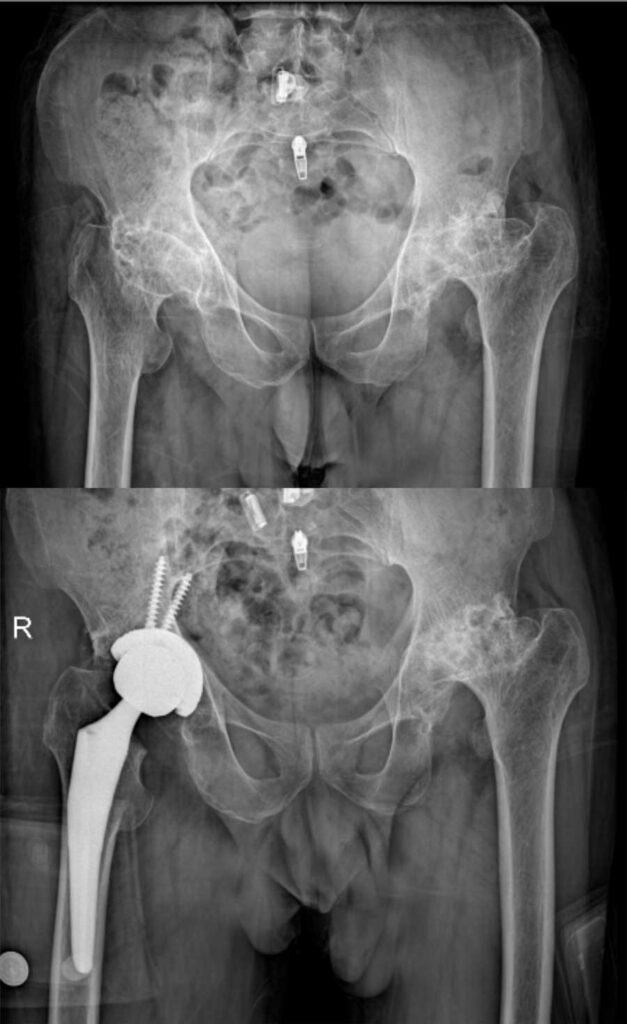

عکس تعویض مفصل لگن

برای آشنایی با تصاویر واقعی رادیوگرافی لگن قبل و بعد از جراحی، عکس تعویض مفصل لگن چند بیمار در زیر وجود دارد. با کلیک بر روی هر کدام از آنها تصویر بزرگتر و کامل را خواهید دید.